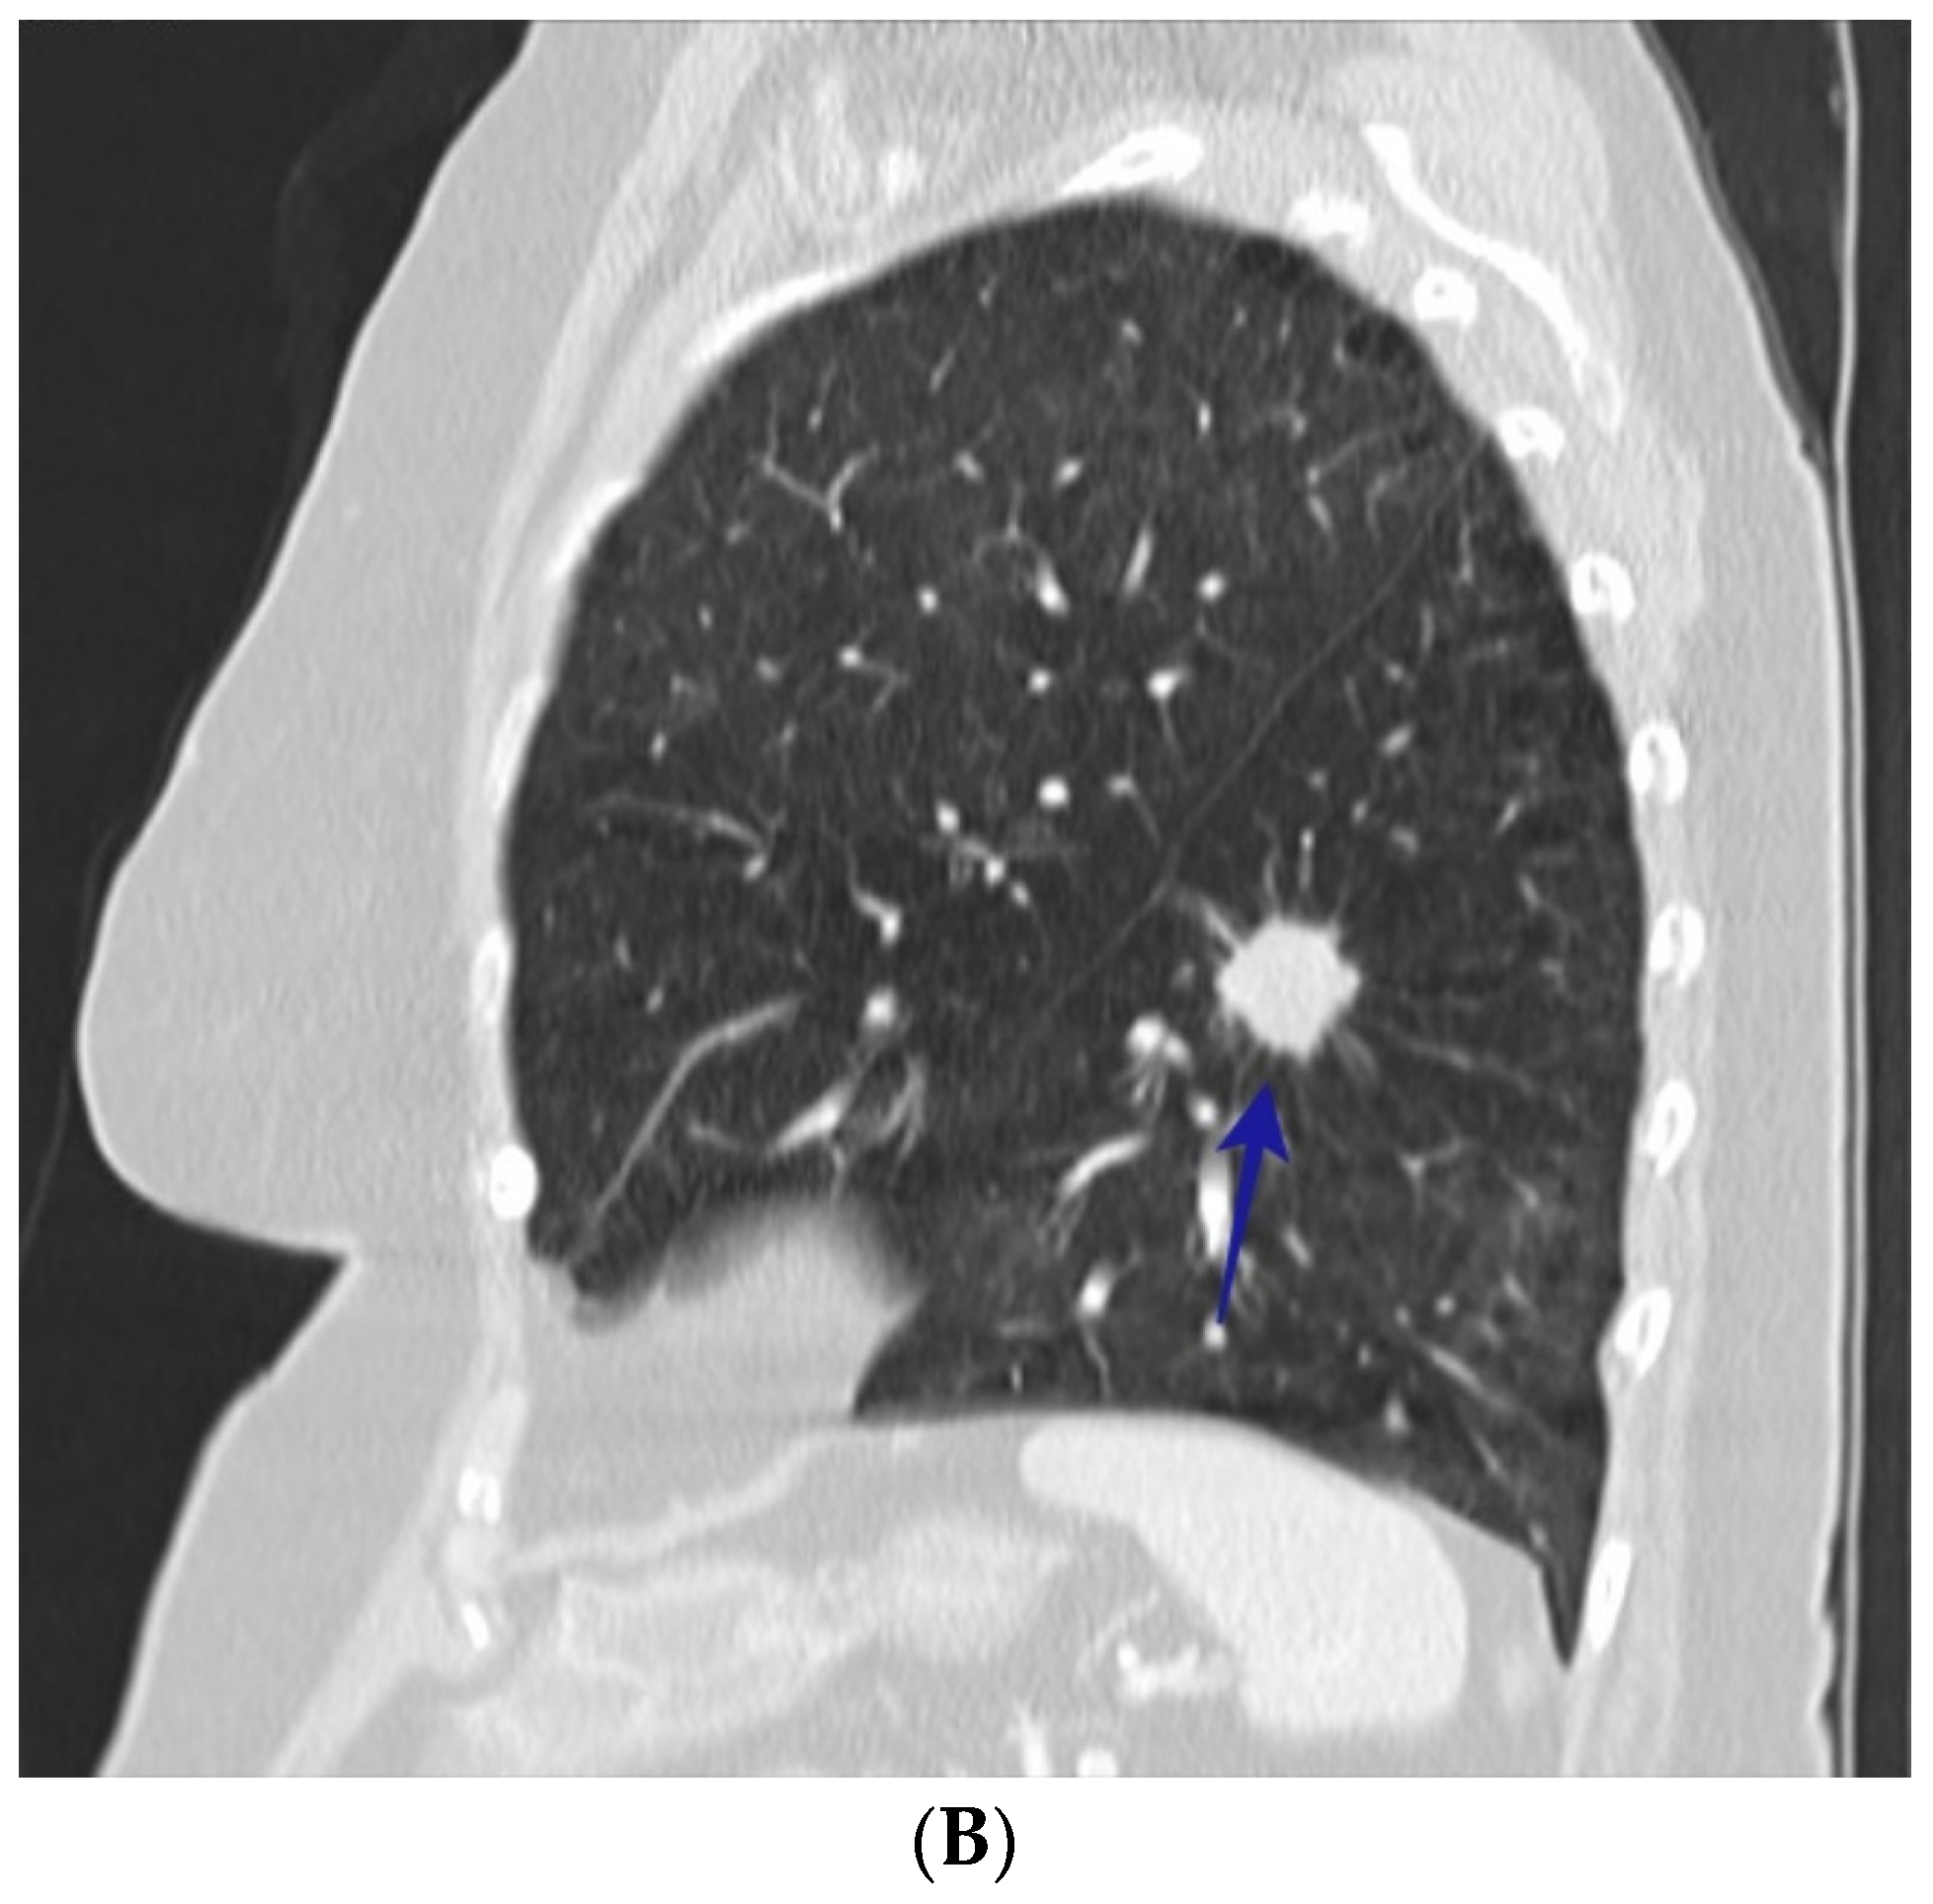

3. Results